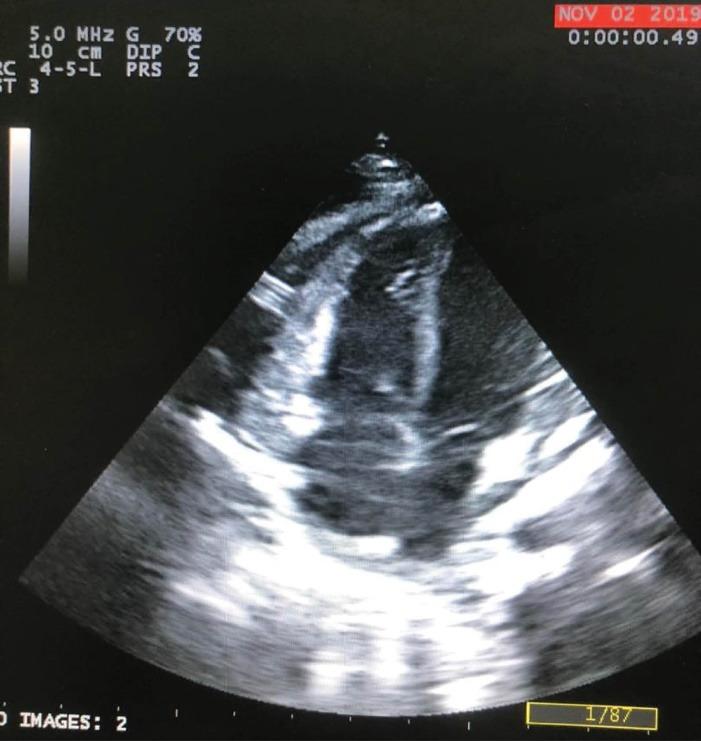

A male infant with a history of ventriculoperitoneal (VP) implantation due to congenital hydrocephalus presented with fever and lethargy at the age of 8 month-old. Pericardial effusion was detected in transthoracic echocardiography, and he underwent pericardial window operation and was discharged in a stable condition. At 11 months of age, he presented again with fever, lethargy, recurrent vomiting, and respiratory distress. In both plain chest radiography and transthoracic echocardiography, VP shunt migration to the heart cavity was observed. The VP shunt had entered into the right ventricle after perforating the diaphragm and pericardium. The patient underwent open-heart surgery due to vegetation at the tip of the VP shunt inside the right heart. Vegetation was removed and the tip of the shunt was returned to the peritoneal cavity. Two weeks after discharge, the patient presented again with symptoms of tachypnea and lethargy. The imaging revealed the entry of the VP shunt about two centimeters into the anterior mediastinum. The patient was transferred to the operation room and the VP shunt was shortened and re-inserted into the peritoneal cavity. Antibiotic treatment was continued for six weeks and the patient was discharged in stable condition. In follow-up visits after two years, the VP shunt functioned well and no particular complication was observed. This case demonstrates that in patients with VP shunt implantation presenting with pulmonary and cardiac symptoms such as respiratory distress, pericardial effusion, and cardiac tamponade after VP shunt implantation, the possibility of VP shunt catheter migration to the mediastinal cavity should be considered.

一名因先天性脑积水接受脑室腹腔(VP)分流术的男婴,8个月大时出现发热和嗜睡症状。经胸超声心动图检查发现心包积液,随后他接受了心包开窗手术,出院时病情稳定。11个月大时,他再次出现发热、嗜睡、反复呕吐和呼吸窘迫症状。胸部X线平片和经胸超声心动图检查均观察到VP分流管移入心脏腔室。VP分流管在穿透膈肌和心包后进入右心室。由于右心室内VP分流管尖端出现赘生物,该患者接受了心脏直视手术。赘生物被清除,分流管尖端被放回腹腔。出院两周后,患者再次出现呼吸急促和嗜睡症状。影像学检查显示VP分流管进入前纵隔约两厘米。患者被转至手术室,VP分流管被缩短并重新插入腹腔。抗生素治疗持续六周,患者出院时病情稳定。在两年后的随访中,VP分流管功能良好,未观察到特殊并发症。该病例表明,对于接受VP分流术的患者,若术后出现呼吸窘迫、心包积液和心脏压塞等肺部和心脏症状,应考虑VP分流管导管移入纵隔腔的可能性。